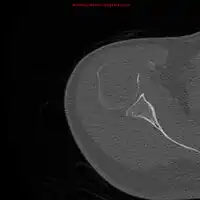

1.a. X-ray: solitary plasmacytoma upper arm near shoulder -

1.b. CT scan: solitary plasmacytoma upper arm near shoulder -